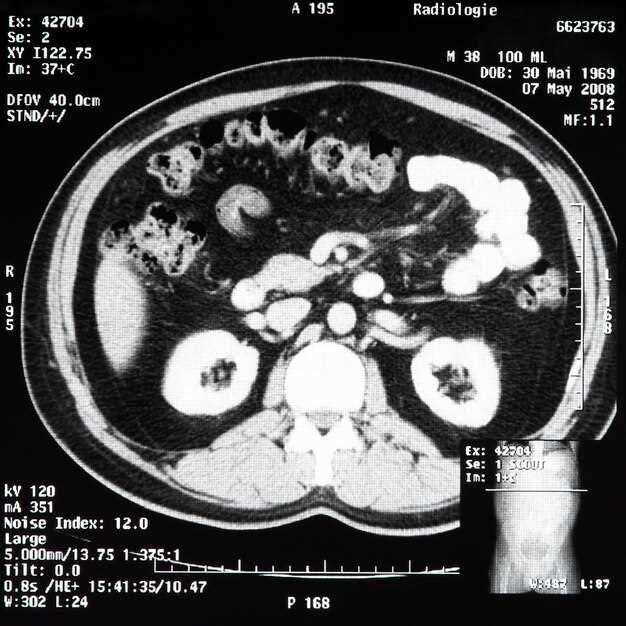

What 99mTc-DTPA + 40 mg Furosemide Actually See That Ultrasound and CT Never Show

My neighbor kept showing up in the ER with “renal colic” that CT called a 3 mm non-obstructive stone. Two ultrasounds later, the radiologist still wrote “no hydronephrosis, cause of pain unclear.” The guy was popping NSAIDs like candy and missing work. One Friday morning we slapped on the 99mTc-DTPA, pushed 40 mg furosemide, and within twelve minutes the left kidney was still squeezing at 32 % perfusion while the right side drained like a bathtub. The Lasix washout curve never dipped; it plateaued. That plateau is a quiet scream that no gray-scale image can translate.

The invisible numbers behind the picture

- Split function per kidney, not guess-work. CT only tells you “both kidneys enhance.” The scan says left 42 %, right 58 %–and whether that 42 % is worth saving before urology yanks the stent.

- Drainage half-life in seconds, not millimeters. Ultrasound can measure pelvic diameter, but diameter is geometry, not flow. A 12 mm pelvis that empties with T½ = 4 min is normal; a 6 mm pelvis that still holds tracer after 20 min is heading for loss of cortex.

- Obstruction under pressure. CT misses the tight UPJ that opens only when the collecting system is stretched by diuresis. The 40 mg furosemide challenge raises urine output 4-6 fold, unmasking the bottleneck that pain reports keep flagging.

- Residual cortical activity. If the parenchyma still grabs tracer, the nephron mass is alive. A silent CT can’t separate scar from stunned tubules; the scan does.